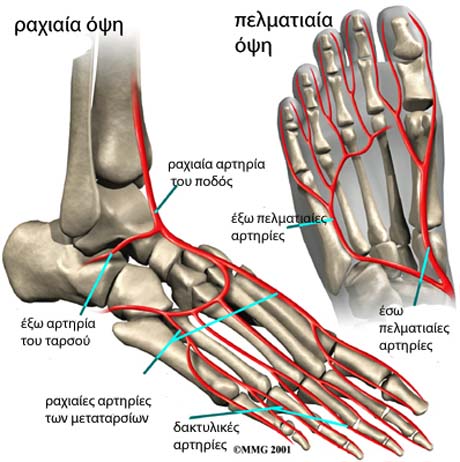

Η οπίσθια κνημιαία αρτηρία αποτελεί την κύρια παροχή αίματος του ποδιού βρίσκεται δίπλα στο κνημιαίο νεύρο περνώντας από το έσω σφυρό. Η ραχιαία αρτηρία του ποδός βρίσκεται στη ραχιαία επιφάνειά του και είναι εύκολα ψηλαφητή.

Οι αρτηρίες του ποδιού.